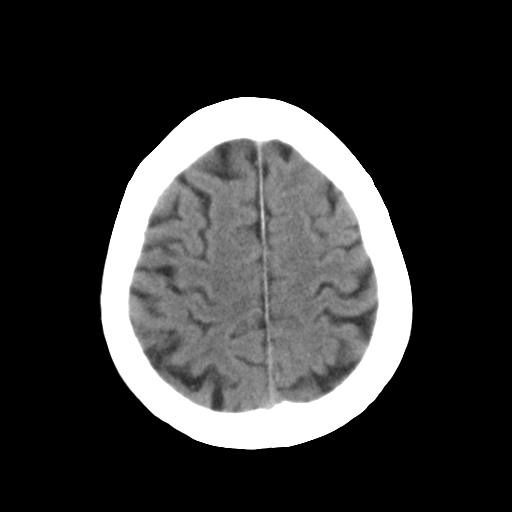

标题: CT25306:男性,75岁。右侧肢体无力一周。 [打印本页]

标题: CT25306:男性,75岁。右侧肢体无力一周。

1)右侧小脑梗塞。2)脑萎缩。